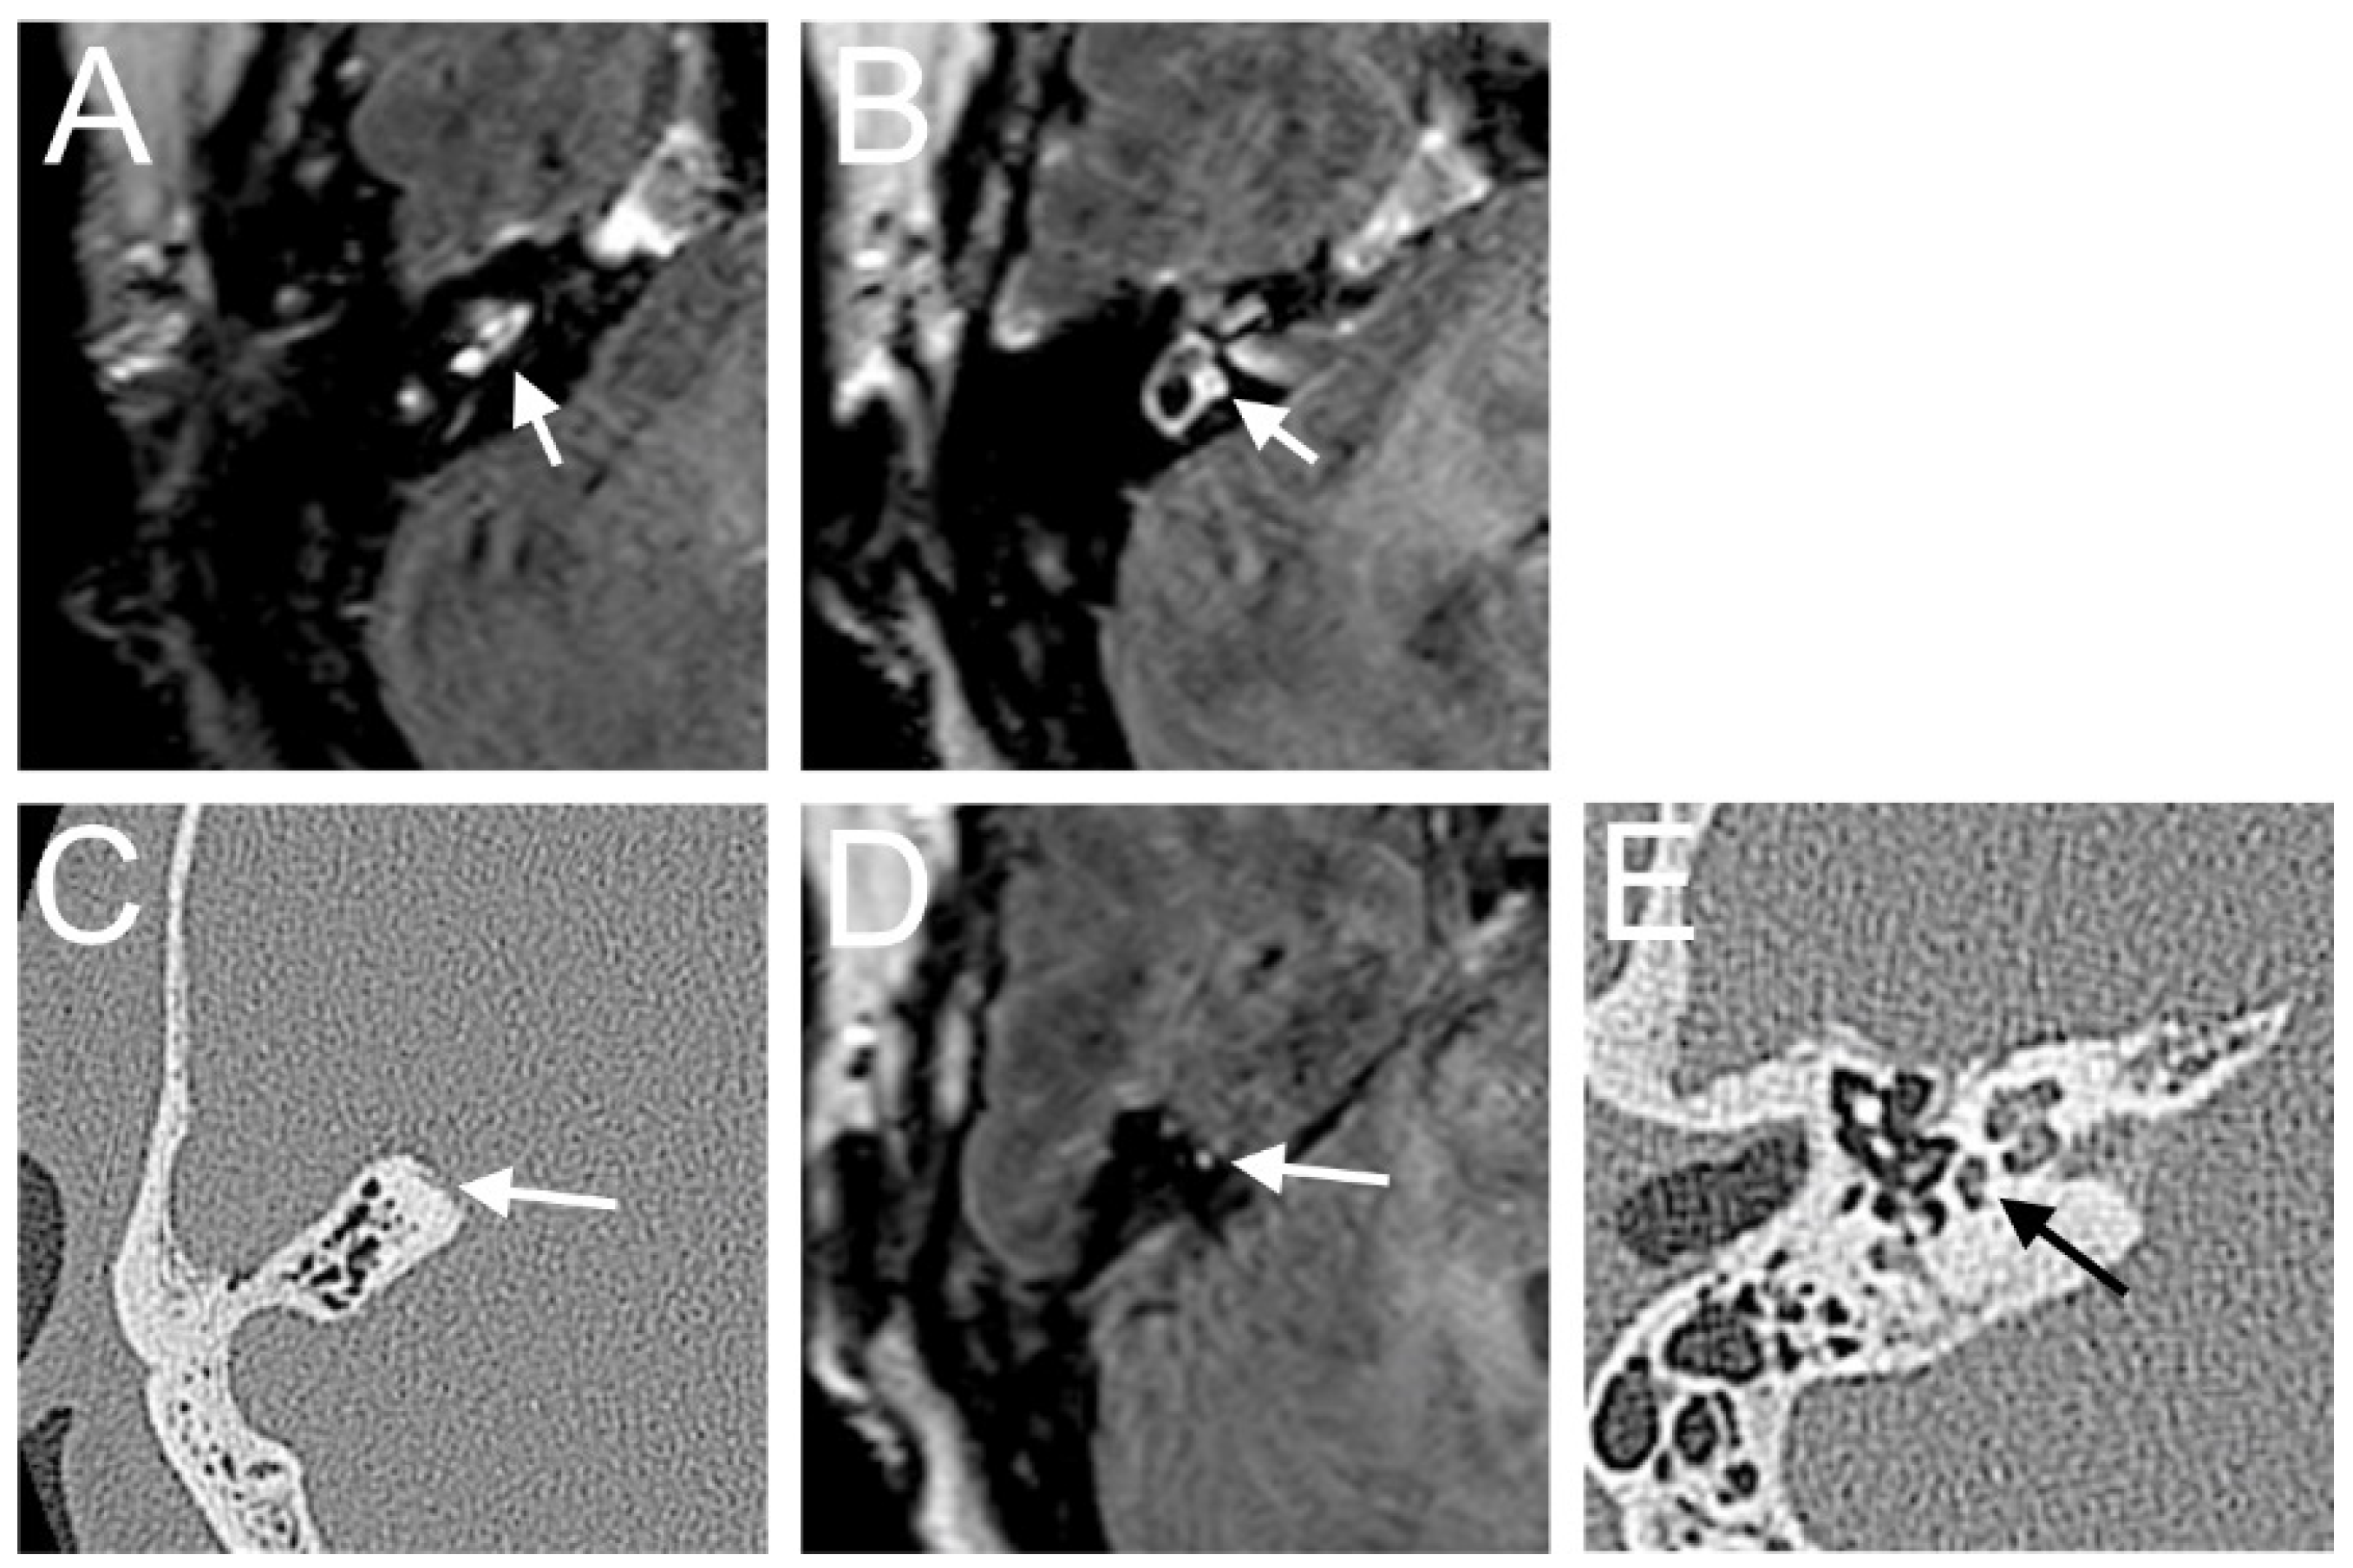

A 48-year-old male presented with a sudden hearing loss on the right side with tinnitus. He showed no vestibular symptoms. The PTA was 110 dB on the right side. Intraoperatively, a PLF track around the RW niche was observed, and the CTP on the right side was positive. A normalized signal intensity of the vestibulum and cochlear was observed on T1W and CE-T1W. A hyperintense signal intensity was found on T2-weighted MRI sequences. On the 4 h delayed 3D-FLAIR image, a contrast enhancement was found in the cochlea, vestibulum, and fundus on the right side of the ear with hearing loss (Figure 3A,B). An RWS was not detected in the affected ear. In this MR sequence, we could also observe a SURI on the right side (vestibular endolymphatic hydrops, grade I) (Figure 3C).

Figure 3. A 48-year-old male presented with a sudden hearing loss on the right side with tinnitus. The axial 4 h delayed 3D FLAIR sequence shows a contrast enhancement in the cochlea basal turn on the right side (A). In the same MR sequence, a vestibulum (arrow (B)) and fundus (dashed arrow (B)) and MR enhancement were observed, as well as an inversion of the saccule (arrow (C)) and utricle (dashed arrow (C)) area ratio.